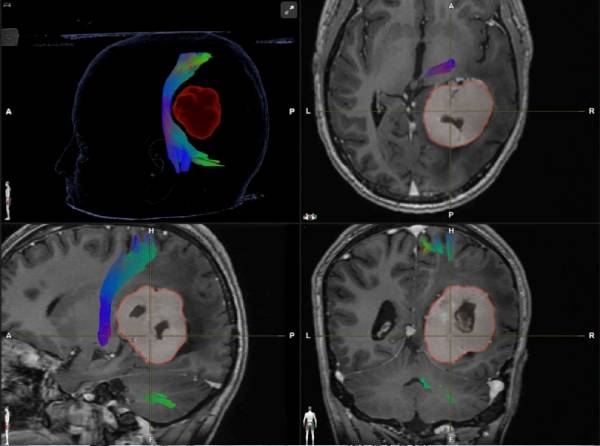

निदान ध्यान से सुनने से शुरू होता है। डॉक्टर आपके लक्षणों को नोट करता है, आपकी ताकत, भाषण और संतुलन की जांच करता है। डॉ. सिंह आगे एमआरआई या सीटी जैसे स्कैन की समीक्षा करेंगे। प्रत्येक रिपोर्ट को सरल शब्दों में समझाया गया है, इसलिए कोई भ्रम या भय नहीं है।

उपचार की योजना चरण दर चरण बनाई जाती है। हर मामले में सर्जरी की जरूरत नहीं होती है। कुछ को दवाओं या नियमित निगरानी की आवश्यकता होती है। यदि सर्जरी की आवश्यकता है, तो सुरक्षा पहले आती है। इसका उद्देश्य सामान्य मस्तिष्क समारोह की रक्षा करते हुए समस्या को दूर करना है। लेकिन अगर आपके शरीर को तत्काल या सस्ती ब्रेन ट्यूमर सर्जरी की आवश्यकता है, तो हम आपका मार्गदर्शन करने और पूरी तरह से ठीक होने तक हर चरण में आपका इलाज करने के लिए हैं।